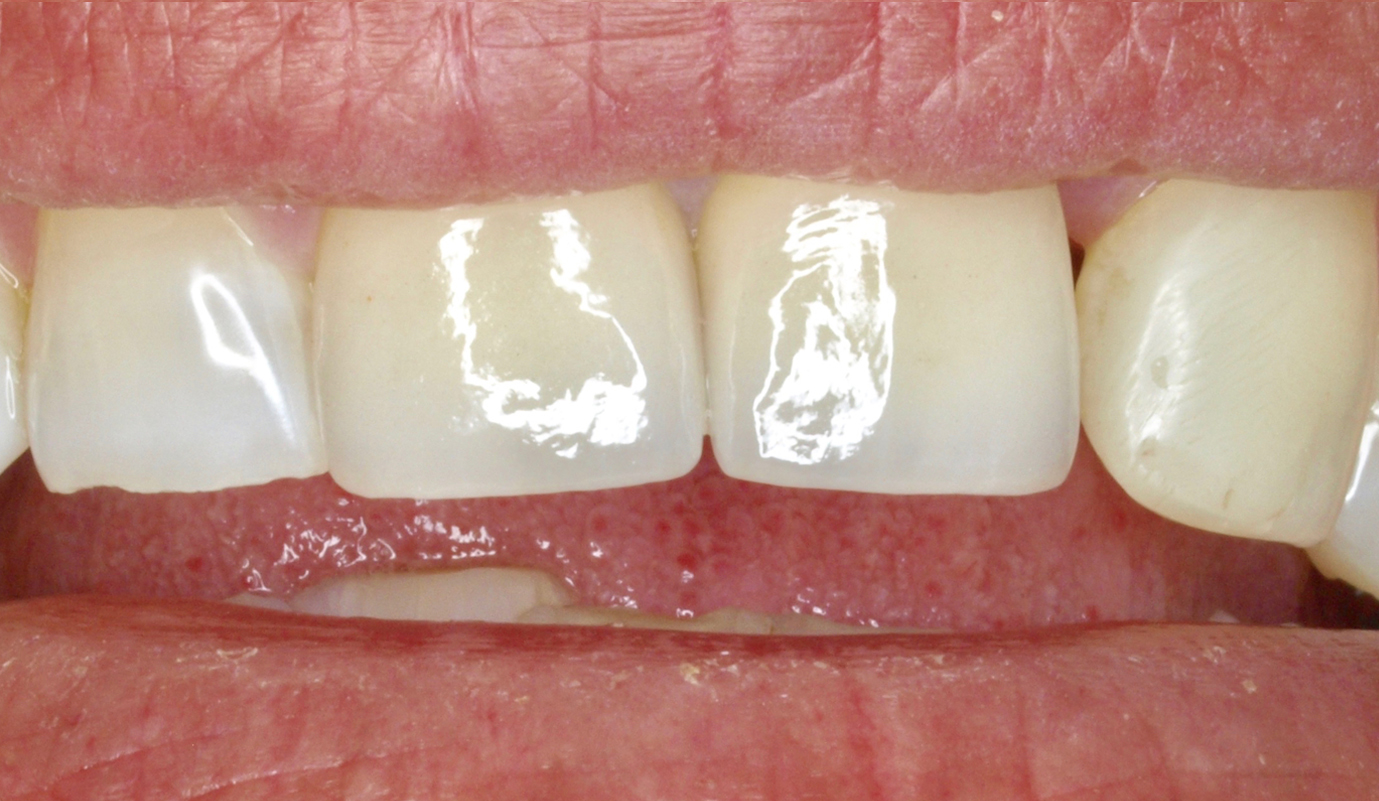

Sobre dentes naturais colocam-se as peças de cerâmica (coroas ou facetas) feitas em Laboratório, a partir de um molde tirado ao dente original. Antes da peça ser colocada sobre o dente, este sofre uma ligeira preparação para que a esta possa ser devidamente aderida ao dente original. Com este tipo de tratamento é possível mudar a cor, a forma, a orientação, o tamanho e mesmo o comprimento dos dentes. Resolvem-se problemas como:

Casos de prótese fixa sobre dentes